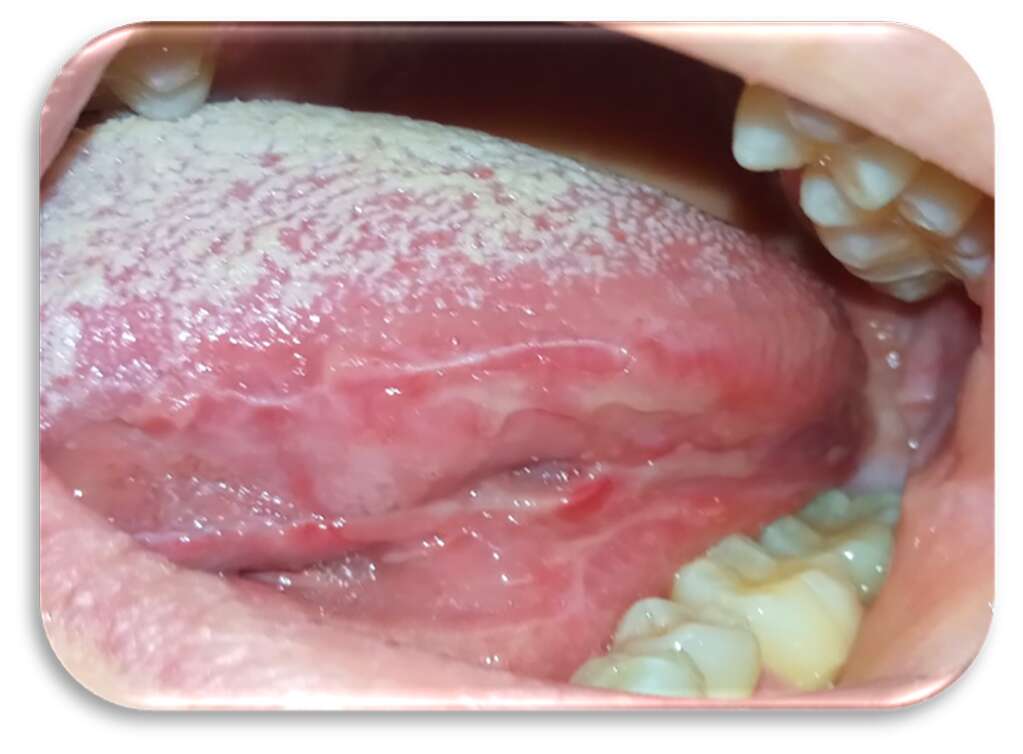

Inizialmente la paziente era stata trattata con collutorio a base di clorexidina 0,2% per circa 12 giorni senza alcun beneficio. Le lesioni si presentavano molto dolenti, erosive ed eritematose bilateralmente e simmetricamente sul ventre linguale (Figure 1 e 2) e sulla mucosa geniena, compatibili con un sospetto quadro clinico di lichen planus orale erosivo.

Sia sui margini linguali che sulle mucose geniene erano presenti, inoltre, segni di morsicatio buccarum e linea alba (Figure 3 e 4).